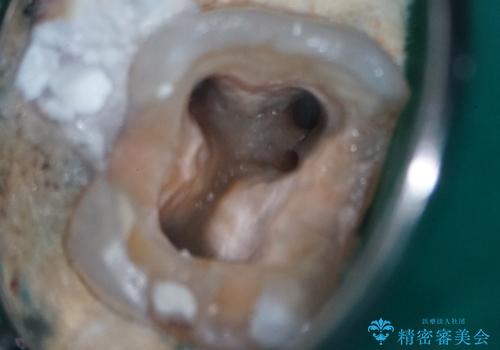

精密根管治療 右上7番に対して、歯科用顕微鏡などを用いた精密根管治療を実施しました。根管内の感染源を徹底的に除去し、緊密に充填。経過観察の結果、根尖病変は完全に消失し、健康な状態を取り戻すことができました。